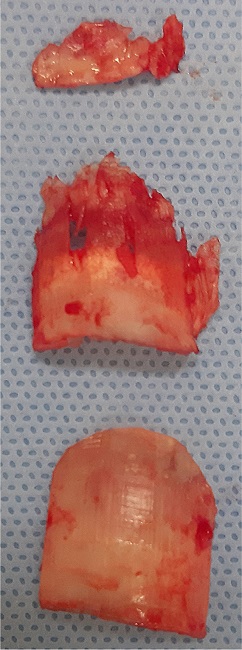

Local anesthesia was performed by anesthetic block (digital, distal, bilateral of the affected hallux) with lidocaine 2% without vasoconstrictor. Subsequently, hemostasis was performed using a number 2 Penrose drain, in a tourniquet, followed by the detachment of the first nail plate and retraction of the proximal nail fold with an electrocautery tip (Figure 4).The detachment of the nail plate evidenced voluminous granulation tissue, which was excised, then proceeding with the removal of the second and third nail plates, in sequence.

Then, the excision of granulation tissue and inflammatory debris was performed in-depth, with total cleaning of the cavity with saline solution. The proximal nail fold was repositioned with the placement of wide-lumen latex surgical drain, with the distal end advancing over the bed to drain postoperative secretions (Figures 5 and 6). We then proceeded to bilateral suture using 5-0 mononylon and applying a bulky containment dressing with mupirocin, gauze, and crepe bandage. The patient was instructed to perform daily dressings, in addition to the use of antibiotics, anti-inflammatories, and analgesics.

The patient had a good postoperative recovery, with clinical improvement (Figure 7).The anatomopathological examination showed chronic ulcerated inflammation with the formation of exuberant granulation tissue in the nail bed (Figure 8).

Thus, in advanced and/or recurrent cases, the surgical approach is more indicated, promoting the resolution of the condition from the avulsion of the overlapping nail plates and excision of the granulation tissue,1,3,6,7 as performed in the reported case. The histopathological examination is not essential for diagnosis; however, it is recommended that the excised material is sent to pathological analysis to exclude the diagnosis of neoplasms of the proximal nail fold, as conducted in this case.

We described the surgical technique adopted in the case of exuberant retronychia without previous clinical response. We observed an abundant amount of granulation tissue intraoperatively, including under the plates, emphasizing the severity and peculiarity of the case, rarely reported in the literature. It’s noteworthy that the technique described is one of the possible options for the surgical treatment of these cases.